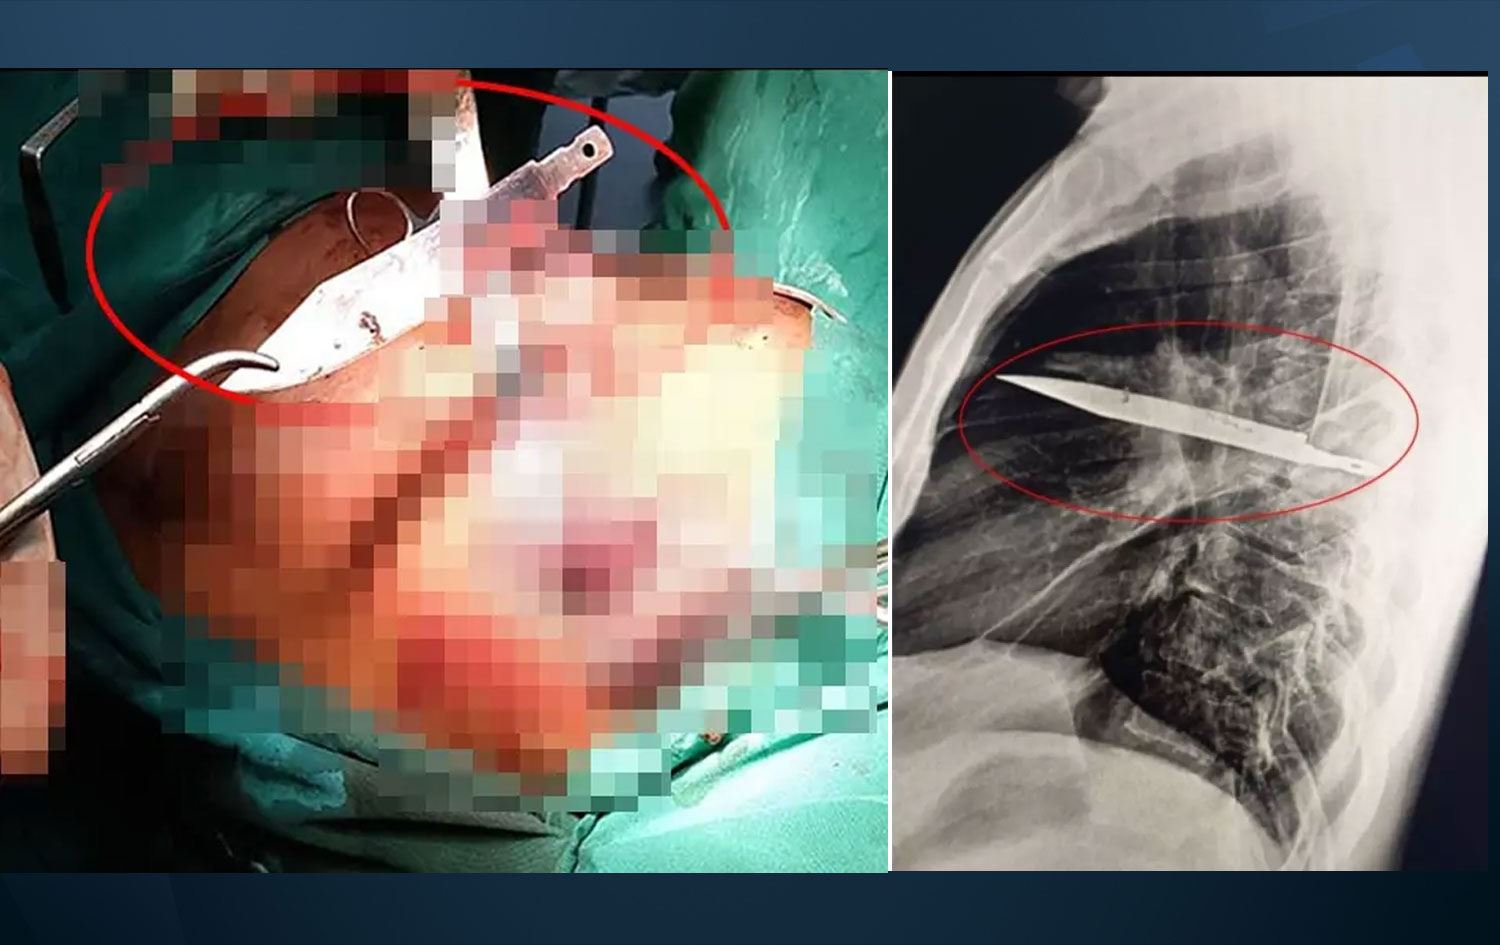

Haber Merkezi - Tanzanya’da bir kişi, iltihap şikâyetiyle gittiği hastanede şoke edici gerçekle yüzleşti. Doktorlar, göğsünde tam sekiz yıldır saplı duran bıçağı ameliyatla çıkardı.

Tanzanya’da 44 yaşındaki bir adam, sağ memesinin altından iltihap akması şikâyetiyle hastaneye başvurdu.

Ancak yapılan röntgen sonucu herkesi şaşkına çevirdi. Adamın göğsünde tam 8 yıldır saplı duran bir bıçak vardı.

Bıçağın sağ kürek kemiğinden girerek hayati organlara zarar vermeden göğüste kaldığı belirlendi.

Yapılan ameliyatla bıçak çıkarıldı ve ölü dokular temizlendi.

Hasta, yoğun bakımda bir gün, normal serviste ise 10 gün kaldı. Doktorlar, yapılan kontrollerde hastanın tamamen iyileştiğini duyurdu.